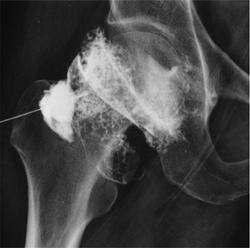

Pigmented Villonodular Synovitis

Pigmented villonodular synovitis (PVNS)

is a relatively uncommon disorder characterized by synovial

proliferation with hemosiderin deposition in synovial tissues. -

The condition may involve joints, bursae, or tendon sheaths.

-

There are diffuse forms (80% involve the knee) and localized forms such as giant cell tumor of the tendon sheath.

The condition is diagnosed most commonly in the second through fifth decades.

PVNS is typically monoarticular involving

the knee followed by the hip, ankle, shoulder, elbow, temporomandibular

joint, and spine. -

Radiographic findings are evident in 80%

of cases. Findings include swelling, joint effusion (often denser than

a simple effusion), and cystic or erosive changes in bone. -

MR features are characteristic with areas

of low signal intensity on T1- and T2-weighted sequences resulting from

hemosiderin deposition. -

Treatment consists of synovectomy.

Recurrence rates are 25% to 50%. Postoperative baseline MR examinations

are recommended for more optimal detection of residual PVNS or

recurrence.

![]() |

|

FIGURE 13-37 PVNS. Sagittal T1- (A) and T2- (B)